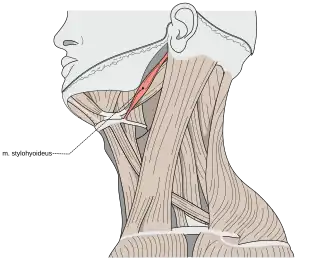

Aunque no existe acuerdo respecto al origen del síndrome, sí lo hay respecto a cómo se producen los síntomas que lo definen. Una elongación u osificación de las estructuras del complejo estilohioideo conlleva una compresión de las estructuras neurovasculares de alrededor, entre las que se hallan los nervios facial, auriculotemporal, lingual, glosofaríngeo o hipogloso. Además, el complejo estilohioideo es el encargado de dividir las arterias carótida interna y carótida externa. Por ello, una compresión o pinzamiento de estas estructuras puede presentar una gran variedad de síntomas.[6]